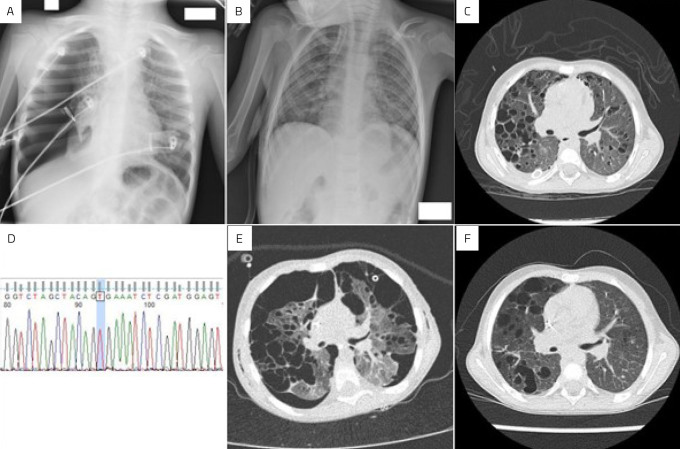

Case description: Case #1: A 3-year-old male patient with a sudden episode of spontaneous right-sided pneumothorax, surgically drained. After 2 months, he experienced two new episodes of contralateral pneumothorax. A pulmonary lymph node biopsy revealed the diagnosis of LCH. He underwent bilateral video-assisted thoracic surgery and mini-thoracotomy with mechanical pleurodesis, in addition to chemotherapy, requiring prolonged hospitalization. Case #2: A 4-year-old boy with progressive dyspnea and wheezing for 5 months. A pulmonary biopsy revealed LCH. He developed significant respiratory distress and right pneumothorax, requiring drainage. Silver nitrate pleurodesis and different chemotherapy regimens were performed. Both patients responded well to multiple chemotherapy treatments, surgeries, and intensive care support.